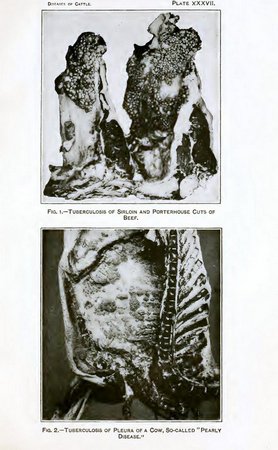

| XXXVII. Fig. 1.—Tuberculosis of sirloin and porterhouse cuts of beef. | |

| Fig. 2.—Tuberculosis of pleura of cow, so-called "pearly disease" | 416 |